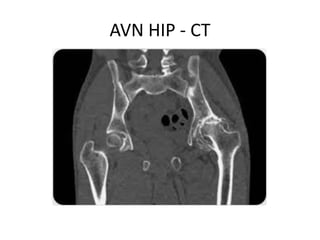

• Plain radiographs are helpful in establishing

the diagnosis

• findings ranging from mottled densities and

lucencies to severe collapse of the femoral

head

• Joint replacement may be required.

AVN HIP - CT